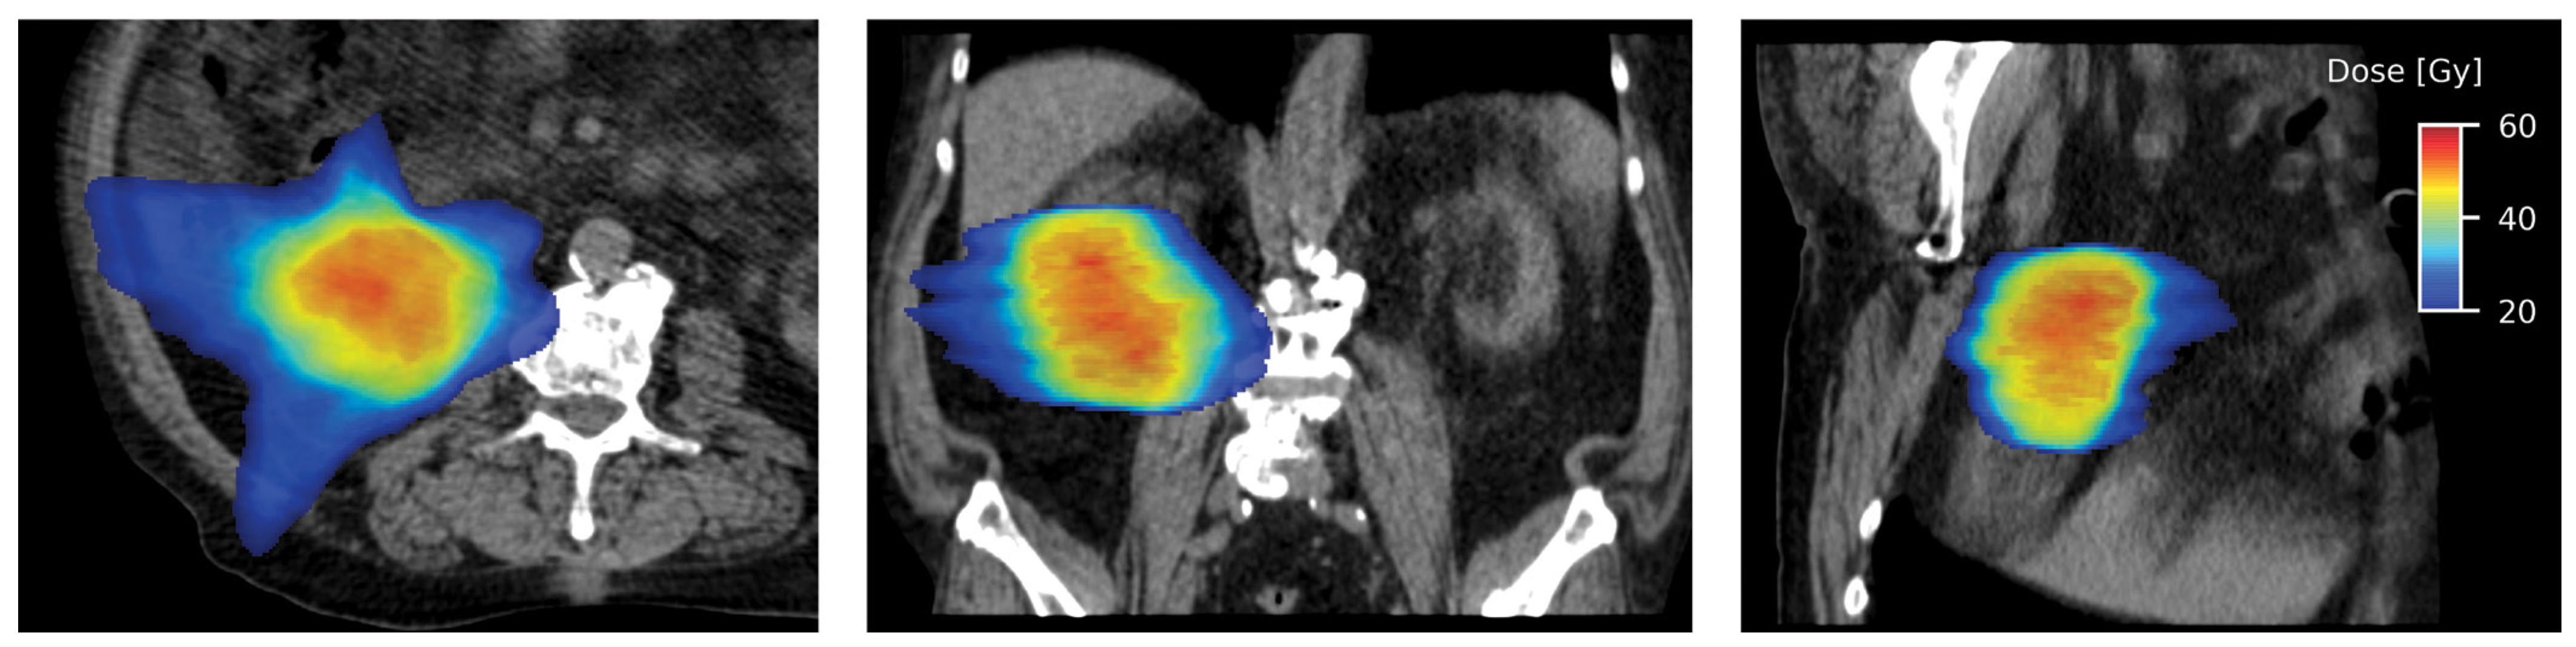

Different treatment units are used to deliver SABR to primary RCC[61,62,65,69,73]. Irrespective of the treatment system used, respiratory motion management is essential for treatment planning and delivery, due to the motion of kidneys with respiration[76]. The most commonly used technique in linear accelerator-based treatment is the internal target volume (ITV) concept, where a thin-cut 4-dimensional CT (4D-CT) is obtained during simulation. Respiratory gating or tumor tracking using implanted fiducial markers may be used to allow for a reduction in ITV, and this is usually incorporated into the delivery of SABR using CyberKnife. A typical linear accelerator-based SABR plan is shown in Figure 2.

Figure 2.

Axial (left), coronal (middle), and sagittal sections (right) showing highly conformal radiation dose distribution with a typical SABR plan.

Target volumes for SABR are defined as per the International Commission on Radiation Units and Measurements report (ICRU) 91[77], which has been suggested previously by the International Radiosurgery Oncology Consortium for Kidney (IROCK) consensus statement as well[78]. Similarly, the IROCK group recommended organs at risk (OARs) with acceptable dose constraints, adapted and summarized in Table 4[78]. The IROCK consensus statement recommended 25–26 Gy, 35–45 Gy, and 40–50 Gy in 1, 3, and 5 fractions, respectively[78].